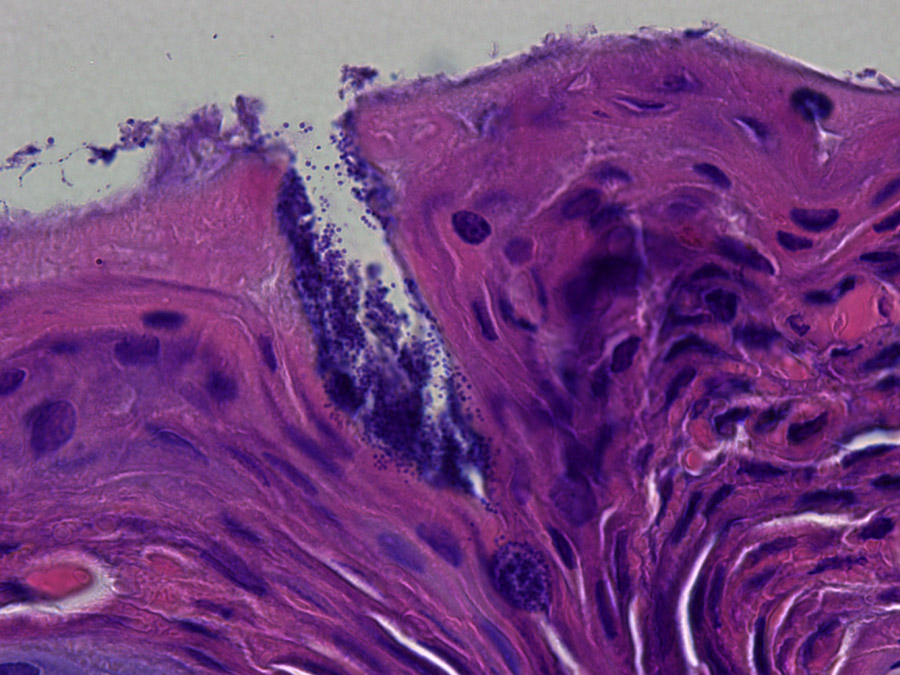

Auf der Abbildung ist die Haut eines Patienten mit Neurodermitis zu sehen (histologische Färbung), die mit Staphylococcus aureus Bakterien (dunkle Punkte auf der Oberfläche und in der Kerbe) bedeckt ist. (Bild: Y. Skabytska / Universität Tübingen)

Weil die Haut und ihre Funktion als Barriere bei Neurodermitis-Patienten stark geschädigt sind, können sich eine Vielzahl von Bakterien ausbreiten – darunter auch Erreger wie das Bakterium Staphylococcus aureus. In vielen Patienten leben fast 200-Mal mehr S. aureus Bakterien auf der Haut als bei gesunden Menschen, was häufige Infektionen zur Folge hat. Prof. Tilo Biedermann und sein Team der Klinik für Allergologie und Dermatologie am Klinikum rechts der Isar und der Universität Tübingen konnten jetzt im Tiermodell zeigen, wie diese Infektionen den Krankheitsverlauf zusätzlich verschlechtern.